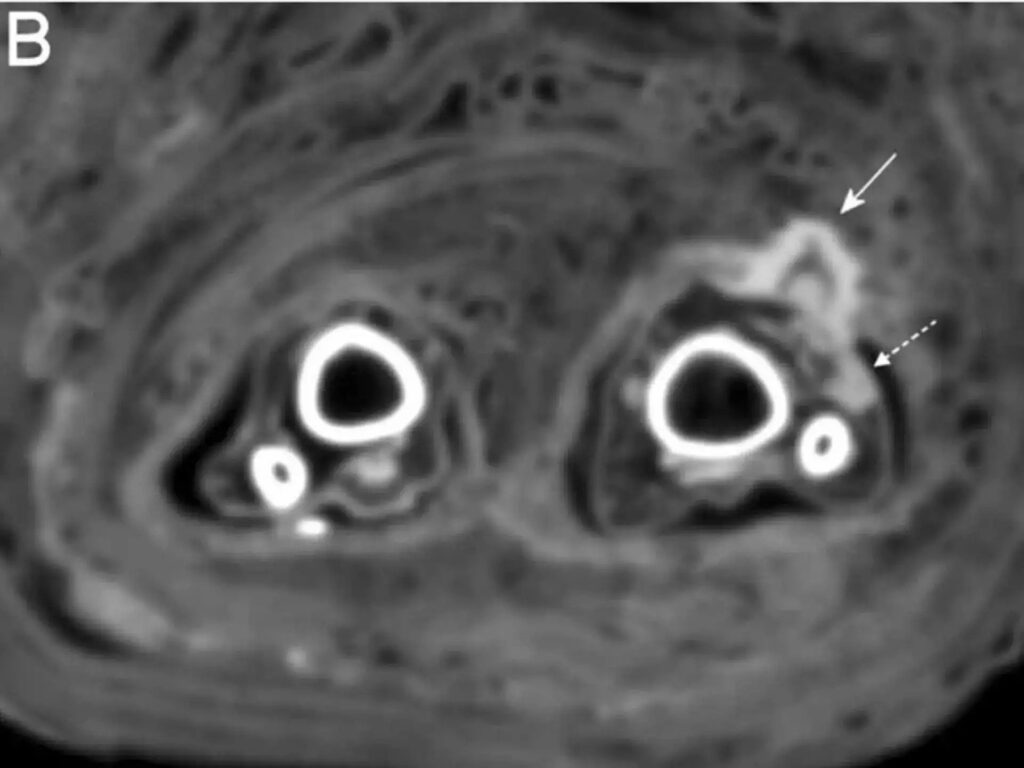

In this case, Zink said, the bandages were spotted while the scientists carried out routine CT scans of mummies, as can be seen in the scans below and annotated with the full-lined arrow. The wound appeared to have been infected when she died, as the scans showed signs of “pus,” Zink said. These signs of infection are marked by the dotted arrows in the scans below.

A cross-section of the mummy’s legs is shown.